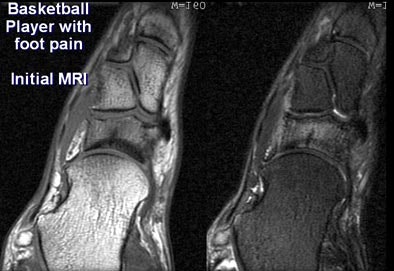

In his presentation, Gold used several case studies from Stanford to illustrate his assessments. First up, a basketball player with foot pain.

CT (0.5-mm reconstructions) revealed only subtle sclerosis of the navicular bone. But MRI showed a region of low signal on T2- and T2-weighted images, surrounded by marrow edema within the navicular bone. "In this case MRI is still somewhat more sensitive (for occult fracture) probably due to the presence of marrow edema," Gold said.

| In a basketball player presenting with foot pain, MRI (below) was better able to show an occult fracture of the navicular bone. All images courtesy of Dr. Garry Gold. |